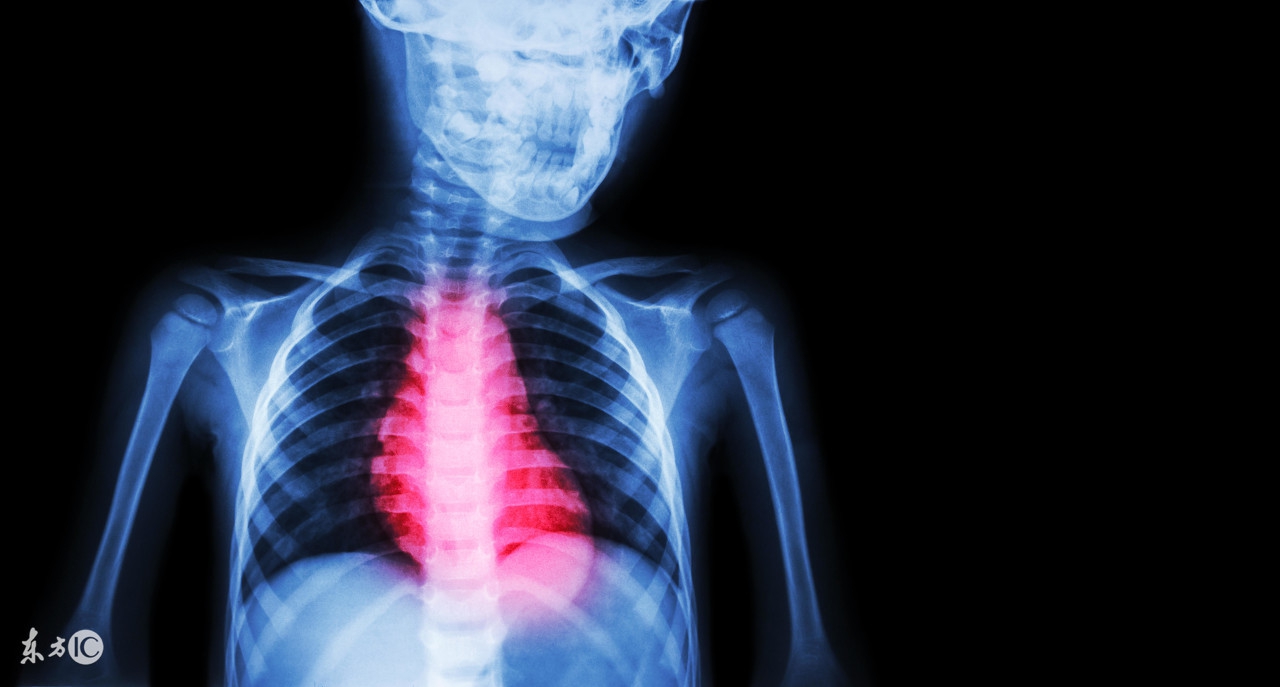

患有心肌缺血的患者朋友在活动量较大或是神经紧张的时候,身体会出现胸闷的情况的,会感觉呼吸不上来,有的时候会有紧缩的疼痛感,还会出现莫名的心悸心慌感的。会有突发心动过缓或是晕厥现象。另外心肌缺血还会有发生心肌梗塞和猝死的危险,因而,因此我们要了解一些关于心肌缺血治疗方面的知识才行的。

心肌缺血如何治疗才好些?缓解心肌缺血,大家要掌握的三个绝招。